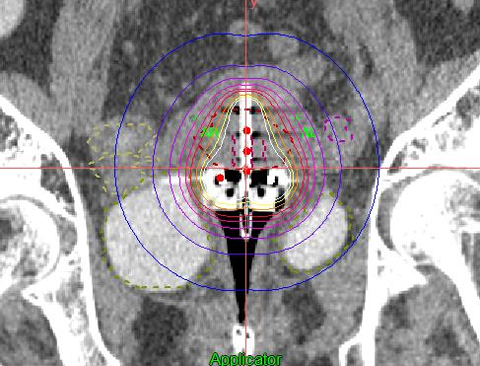

近年、通常の腔内照射に組織内照射を併用するハイブリッド腔内照射と呼ばれる照射方法が普及してきています。

当院は県内で唯一、このハイブリッド腔内照射を施行可能な施設です。

従来の治療法が困難とされる症例にも放射線をより効果的に照射することが期待されています。